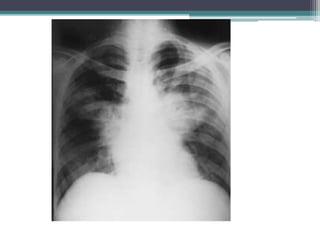

Radiografía de tórax con infiltrado

macronodular basal y medio, múltiple.

Caso Clínico Femenino de 12 años de edad con antecedente de atopia. Inició 15 días previos con mal estado general, hiporexia, astenia, adinamia e ictericia; se manejó como hepatitis en una clínica periférica. Cinco días después se agregó fiebre, tos en accesos y dificultad respiratoria progresiva con cianosis distal; se ingresó a terapia intensiva pediátrica con intubación nasotraqueal y ventilación mecánica. Radiografía de tórax con infiltrado macronodular basal y medio, múltiple.

• Se manejócomo neumonía de focos múltiples con dicloxacilina más amikacinay aminas vasopresoras. Las baciloscopias, reacción cutánea a PPD (derivado proteico purificado) y cultivo de lavado bronquial se reportaron negativas para M. tuberculosis.Presentó mala evolución hemodinámica e infectológica, con hemocultivo positivo para Staphylococcus aureus; se cambió el esquema de antibióticos a cefuroxima, clindamicina y amikacina. Mala evolución ventilatoria con síndrome de insuficiencia respiratoria aguda progresiva, requiriendo parámetros ventilatorios altos, ameritó colocación de sello pleural por neumotorax. Posteriormente la radiografía de tórax mostró imágenes de bulas (Fig. 2). Perfil de hepatitis viral A y B negativos; por mala evolución clínica, al cuarto día de estancia se amplió esquema con anfotericina B para cobertura empírica de hongos. Al quinto día de estancia hospitalaria falleció